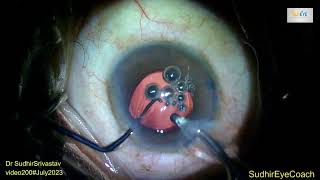

Descemet's Membrane Detachment(DMD) prevention and management video

Descemet's Membrane Detachment(DMD) prevention and management

Descemet's Membrane Detachment(DMD) prevention and management Descemet membrane detachment (DMD) during stromal hydration

Descemet's Membrane Detachment(DMD) prevention and management

Descemet's Membrane Detachment(DMD) prevention and management Descemet membrane detachment (DMD) during stromal hydration